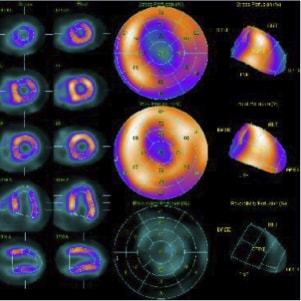

〈負荷心筋シンチグラフィー〉

〈負荷心筋シンチグラフィー〉冠動脈から心筋への血流がわかります